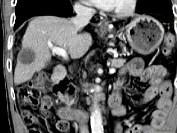

问题 男,63岁,肝区疼痛不适1个月,皮肤巩膜无黄染,AFP高于正常,CT所见如图,最可能的诊断是()

选项 A.肝血管瘤 B.肝转移瘤 C.阿米巴肝脓肿 D.不典型肝癌 E.胆管细胞癌

答案 D